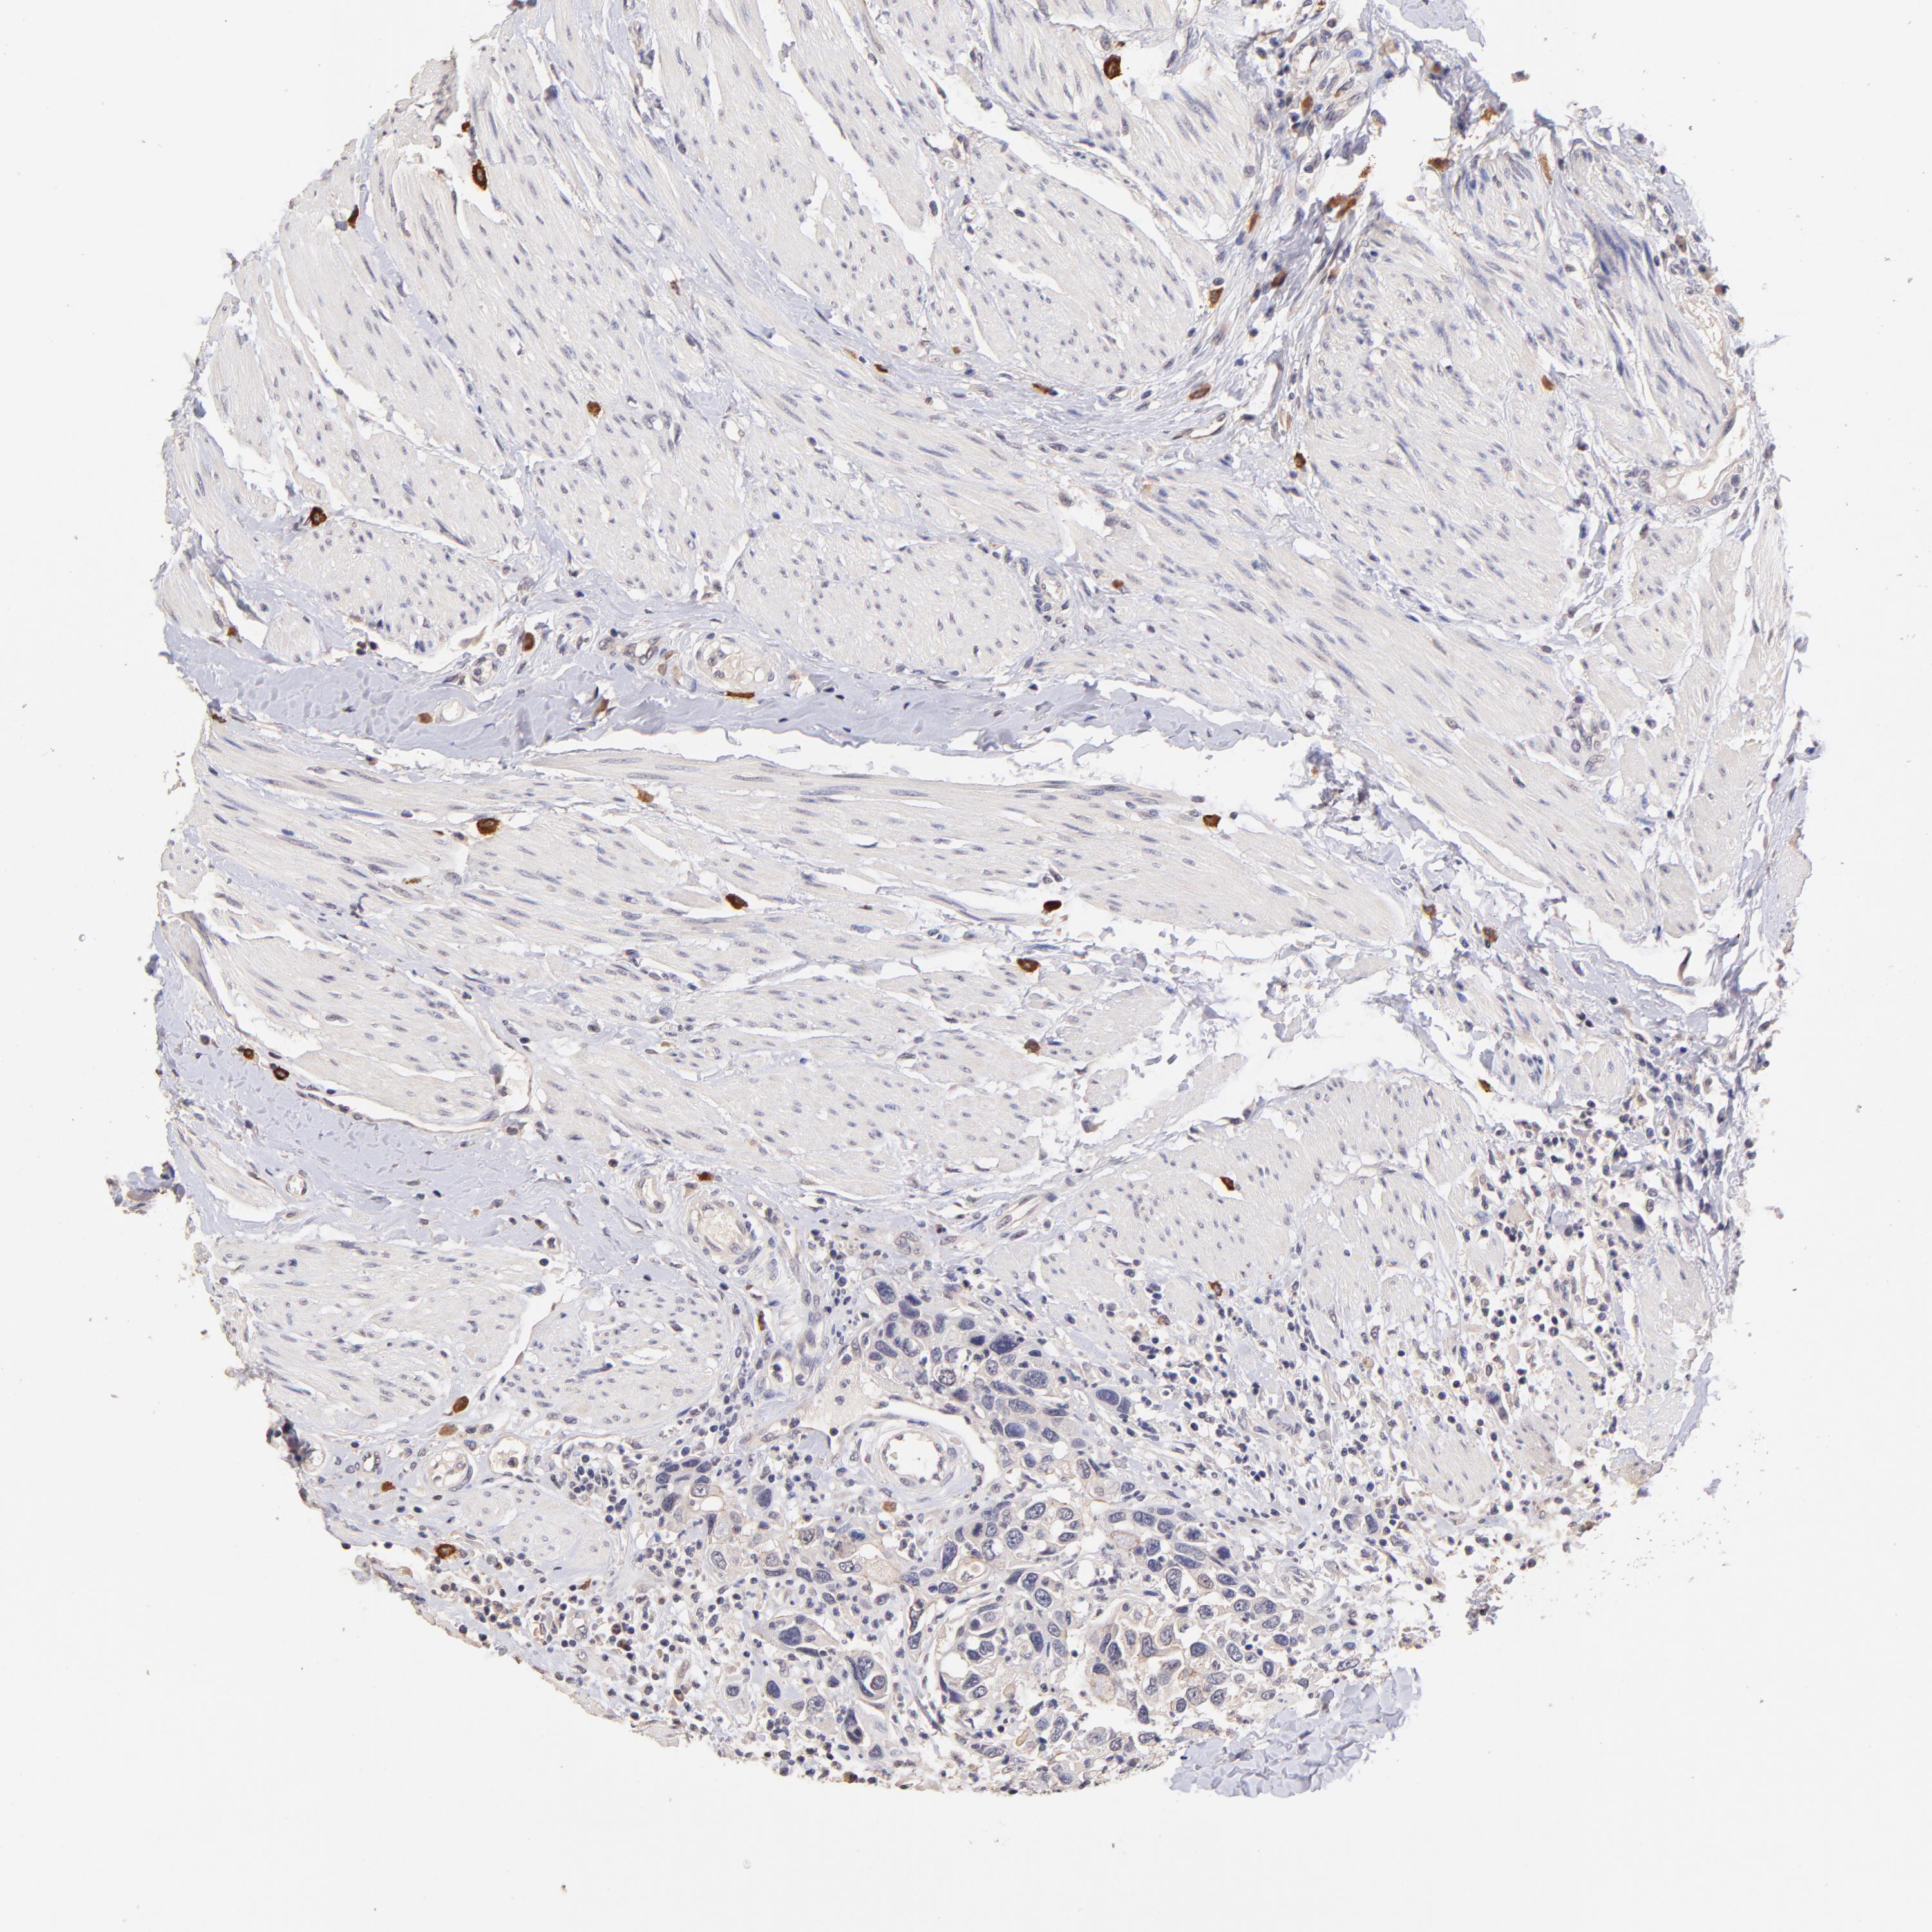

UROTHELIAL CANCER - Protein expressioni

A mouse-over function shows sample information and annotation data. Click on an image to view it in a full screen mode. Samples can be filtered based on level of antibody staining by selecting one or several of the following categories: high, medium, low and not detected. The assay and annotation is described here.

Antibody stainingi

Antibody staining in the annotated cell types in the current human tissue is reported as not detected, low, medium, or high, based on conventional immunohistochemistry profiling in selected tissues. This score is based on the combination of the staining intensity and fraction of stained cells.

Each image is clickable and will lead to virtual microscopy that enables deeper exploration of all samples and also displays staining intensity scores, fraction scores and subcellular localization as well as patient and tissue information for each sample.

Antibody HPA002633

Antibody HPA046758

Antibody CAB010906

Staining

High

Medium

Low

Not detected

Intensity

Strong

Moderate

Weak

Negative

Quantity

>75%

75%-25%

<25%

None

Location

Nuclear

Cytoplasmic/membranous

Cytoplasmic/membranous,nuclear

Urothelial carcinoma, High grade

Urothelial carcinoma, Low grade